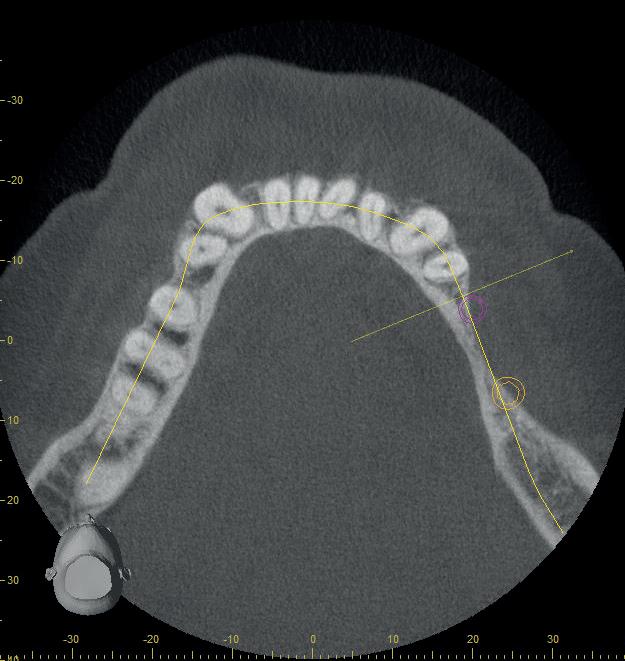

Mevrouw X (afbeelding 1) meldt zich met een desolate dentitie in de bovenkaak en een duidelijke wens voor een vaste voorziening na extractie. Diagnostische gegevens worden verzameld via fotografie, CBCT (Sidexis), een 3D-scan (3Shape) en een digitale facebow-registratie (MODJAW). Al deze gegevens worden samengebracht in SmileCloud, waar behan-

delaren, tandtechnici en ondersteunend personeel toegang hebben tot het dossier en gemakkelijk kunnen overleggen.

SmileCloud maakt het mogelijk om een voorstel (mock-up) uit de DSD-database te genereren dat per tand kan worden gepersonaliseerd (afbeelding 2a en b). Zodra het restauratieve einddoel duidelijk is, kan de implantologie worden gepland. Voor een esthetisch resultaat zijn bothoogte, gingivale dikte en het ontwerp van de tijdelijke restauratie cruciaal. Hier biedt het VEX-model uitkomst (afbeelding 3a-c). Dit model (Virtual Extraction Model) maakt het mogelijk om het implantaat, het abutment én de restauratie virtueel in te plannen. Zo kun je bijvoorbeeld zones van overdruk of onderdruk herkennen, problemen met de gingiva voorzien, het emergence profile